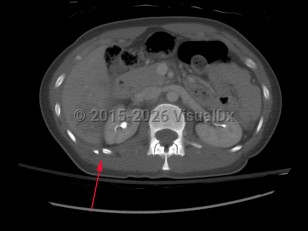

Causes / typical injury mechanism: Rib fractures are a common injury of the thoracic cage. They may be traumatic or pathologic. Depending on the location and the number of ribs involved, be alert for possible visceral injuries, pulmonary contusions, pneumothorax, or vascular injury.

Fractures of the lower ribs (9-12) could indicate concomitant intraabdominal injury.